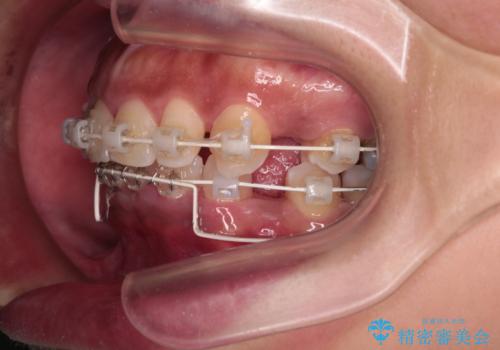

- 矯正装置

- 審美装置

- 下顎前歯部には叢生が認められ、口を自然に閉じにくい状態でした。また、噛み合わせが深い「ディープバイト」の状態で、見た目だけでなく将来的な奥歯への負担も懸念されました。

口元の突出感を改善するため、上下左右の小臼歯4本を抜歯する矯正治療を計画しました。

「矯正装置が目立つのは避けたい」というご希望があったため、プラスチックブラケット+コーティングワイヤーを使用した審美装置を選択しました。